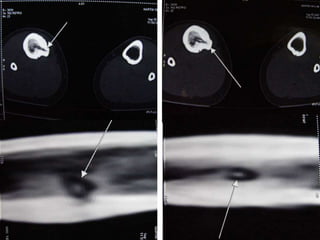

• Excision of the osteoid osteoma nidus using

CT–assisted localization, a Kirschner wire

inserted into the nidus, and a biopsy punch

inserted over the Kirschner wire into the

bone.

• They recommend using a trephine 2 mm

larger than the lesion for complete removal.

• A CT guided needle was passed to localize the

lesion.

• Through an anterior "Hernia" approach the

lesion was approached and excised.

• The Follow-up CT Scanning done to reveal

complete removal of lesion.

• A biopsy confirmed it later.

CT – Guided Drilling

•

OPD procedure,

Localization of the nidus in CT Scan,

Local anesthesia,

K-wire passed into nidus,

Transferred to OT,

Short GA,

Drilling of the nidus by a cannulated drill,

Complete relief of pain.